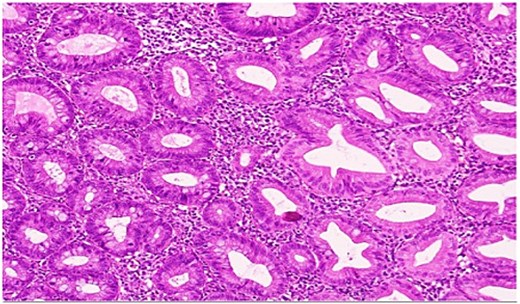

She underwent an uncomplicated laparoscopic appendectomy. Histopathology confirmed acute appendicitis and incidentally identified a serrated polyp confined to the mucosa without dysplasia or malignancy (Figs. 2—4). Postoperative recovery was uneventful; she was discharged stable and asymptomatic at 2-week follow-up. Given the incidental finding, colonoscopic evaluation was arranged to assess for synchronous colorectal lesions.

Low-power hematoxylin and eosin-stained sections of the appendix (4× and 10× magnification) demonstrating prominent crypt serration within the appendiceal mucosa with the characteristic saw-toothed crypt architecture and increased mucin production.